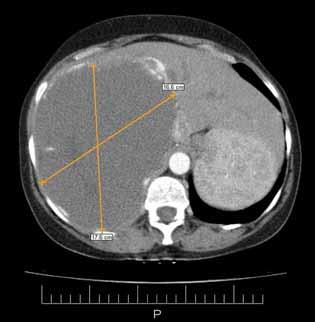

Rycina 38.39. (A–C)